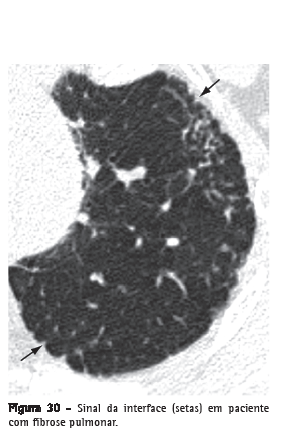

InterfaceSuperfície de separação entre duas estruturas ou espaços. Quando duas estruturas torácicas com diferentes densidades radiológicas se encontram, seus limites são nítidos. Por exemplo, vasos com densidade de partes moles em contato com a densidade de ar do pulmão arejado circunjacente. O "sinal da interface" define a irregularidade das margens entre diferentes estruturas intratorácicas, tais como vasos, brônquios e superfícies pleurais, em geral em decorrência de doença intersticial que causa fibrose (Figura 30).(3)